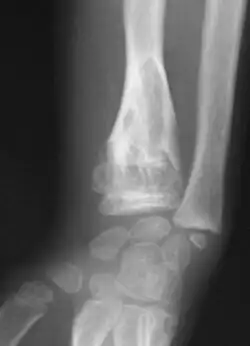

X-ray showing enchondromas localized in the lower part of the radius of a 37-year-old patient affected with Ollier disease -